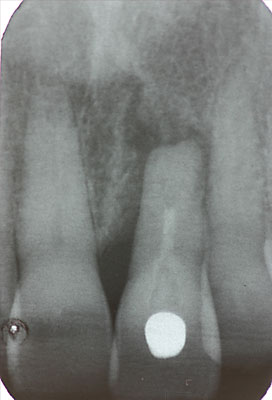

Fall: Einzelzahnlücke nach Zahnextraktion

![]() |